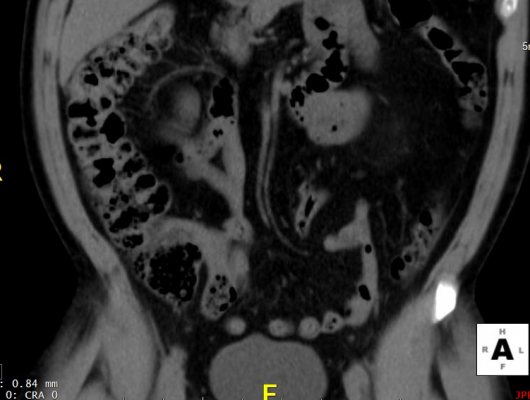

Virtual colonoscopy is an American Cancer Society-recommended screening exam that has been shown in studies in the United States and abroad to increase screening rates where offered. Virtual colonoscopy has been proven comparably accurate to colonoscopy in most people of screening age — including those ages 65 and older. President Obama received a virtual colonoscopy in his first checkup as Commander-in-Chief.

A recent major study shows that screening Medicare patients with CT colonography would reduce CRC screening costs by 29 percent and save Medicare up to $1.7 billion per screening cycle. CIGNA, UnitedHealthcare, Anthem Blue Cross Blue Shield and many other insurers cover screening virtual colonoscopy. More than 20 states require insurers to cover these exams. Today’s USPSTF recommendations, under the Affordable Care Act, would now require all private insurers who take part in insurance exchanges to cover beneficiaries for CTC and the other USPSTF-recognized tests.